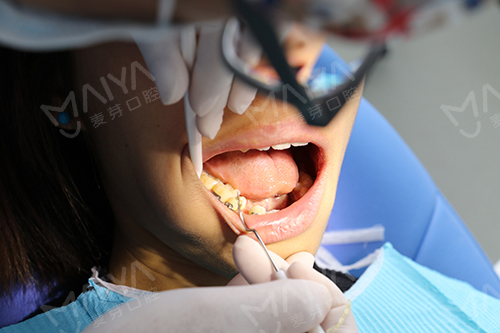

张超主任在为何小姐检查

口腔检查